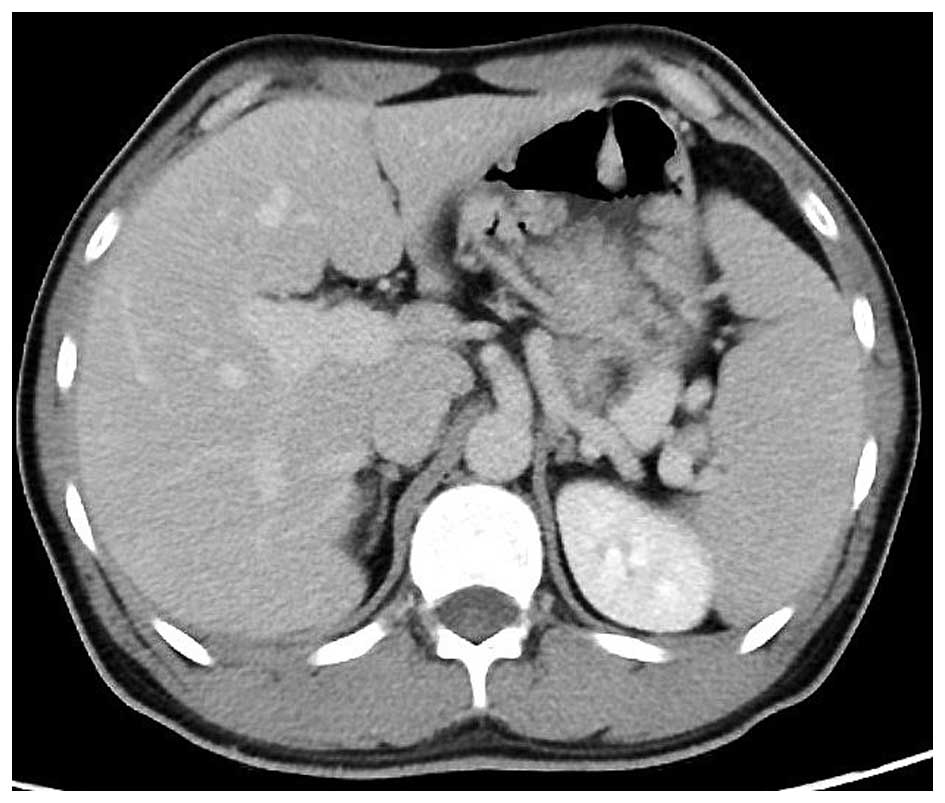

A 24-year-old man with an unremarkable medical history was referred to Onomichi General Hospital (Hiroshima, Japan) as a result of melena and anemia in 2004. An upper gastrointestinal endoscopy in 2004 revealed multiple edematous polyps around the fundus of the stomach (Fig. 1). Histological examination revealed a hyperplastic and disorganized foveolar epithelium, and an edematous lamina propria with infiltration of inflammatory cells, and the histological diagnosis was hyperplastic polyps. The patient began taking a proton-pump inhibitor and iron supplements, and he underwent an upper gastrointestinal endoscopy annually. The polyps appeared around the fundus in 2004 and had gradually progressed to the entire stomach in 2014 (Fig. 2). The number and size of the polyps had also increased. Endoscopic mucosal resection was performed frequently due to bleeding from the polyps. It was difficult to control the progressing anemia by non-surgical treatment, and, in 2014, histological examination revealed for the first time that the benign polyps were adenocarcinoma. Surgical treatment was therefore performed. At the time of surgery, the patient was 171 cm tall and weighed 62.5 kg. No skin lesions or loss of hair, which is characteristic of Cronkhite-Canada syndrome, was exhibited. Laboratory data demonstrated mild anemia (hemoglobin, 9.6 g/dl), but neither hypoproteinemia nor elevation of tumor markers, including carcinoembryonic antigen and carbohydrate antigen 19–9 was observed. With respect to the patient's family history, the patient's mother had succumbed to colon cancer in her 50s and his cousin had succumbed to an unknown primary cancer in his 30s. Colonoscopy revealed no specific findings. Enhanced computed tomography revealed that the stomach wall was edematous with enhanced thickening from multiple polyps (Fig. 3). An upper gastrointestinal series revealed that multiple polypoid lesions were limited to the entire stomach and were not present in the small intestine (Fig. 4). The patient underwent laparoscopy-assisted total gastrectomy with Roux-en-Y esophagojejunostomy. The resected specimen revealed numerous diffuse polyps throughout the entire stomach (Fig. 5). Microscopic findings revealed a hyperplastic and disorganized foveolar epithelium with an atypical nuclear shape. Enlargement of the nucleolus was also observed, and the patient was diagnosed with well-differentiated adenocarcinoma. A total of three lesions of early gastric cancer, and no lymph node metastasis were detected. Immunohistochemical staining revealed that the specimen was positive for p53 and carcinoembryonic antigen and exhibited a high index of mindbomb E3 ubiquitin protein ligase 1 (Fig. 6). The postoperative course was uneventful, hemoglobin level returned to the normal range, and the patient experienced no recurrence over a 1 year follow-up.

Figure 3.

Enhanced computed tomography of the abdomen. Enhanced computed tomography of the stomach wall revealed that the stomach wall was edematous and enhanced, with thickening from multiple polyps.